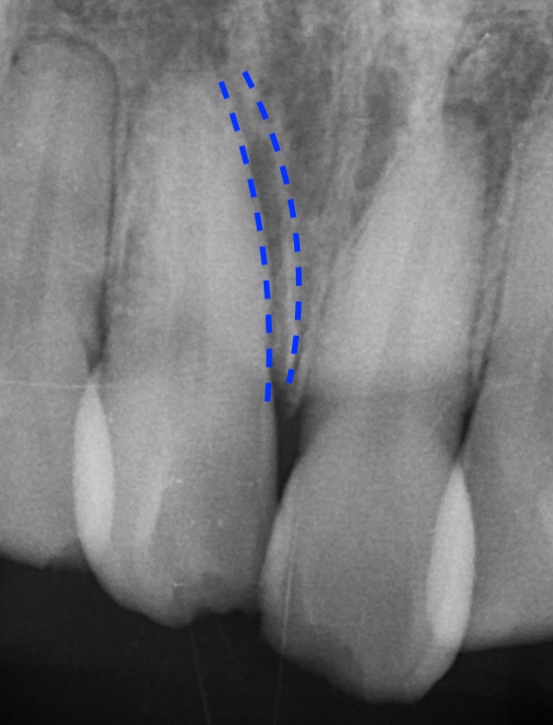

画像は強い外傷を受けた場合で右の点線から左の

点線に歯が移動しています。